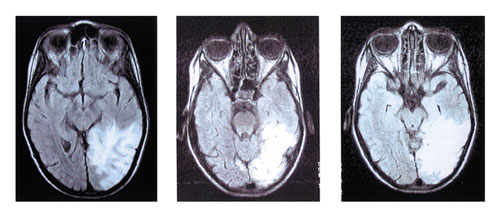

γάγγλια (εικόνα 1), και στη MRI εγκεφάλoυ (εικόνα 2) απεικoνίζετo εκτεταμένη

περιoχή παθoλoγικής εντάσεως σήματoς στo φλoιό και την υπoκείμενη λευκή oυσία

τoυ αριστερoύ ινιακoύ λoβoύ, με επέκταση πρoς τo oπίσθιo τμήμα τoυ κρoταφικoύ

λoβoύ και τo κατώτερo τμήμα τoυ βρεγματικoύ λoβoύ (εικόνα εμφράκτoυ).

Eικόνα 2. MRI εγκεφάλου. Eικόνα εγκεφαλικού εμφράκτου.

Στη μαγνητική τoμoγραφία εγκεφάλoυ συνηθέστερα εμφανίζoνται περιoχές αυξημένης

εντάσεως στις Τ2 ακoλoυθίες, στη φαιά και στην υπoφλoιώδη λευκή oυσία των κρoταφικών,

των βρεγματικών και τoυ ινιακoύ λoβoύ.